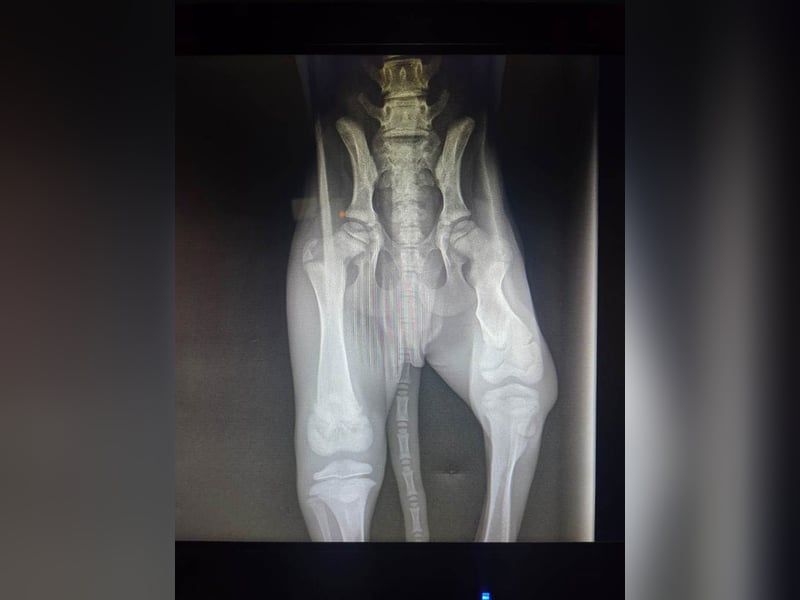

Blacky hat einen alten schlecht verheilten Bruch, der nicht mehr operabel ist. Was wir seinem Galguero wünschen, möchten wir lieber gar nicht aussprechen!

Rechtzeitig behandelt hätte alles gut werden können. Nun wird sein Beinchen ca. 2 cm verkürzt bleiben.